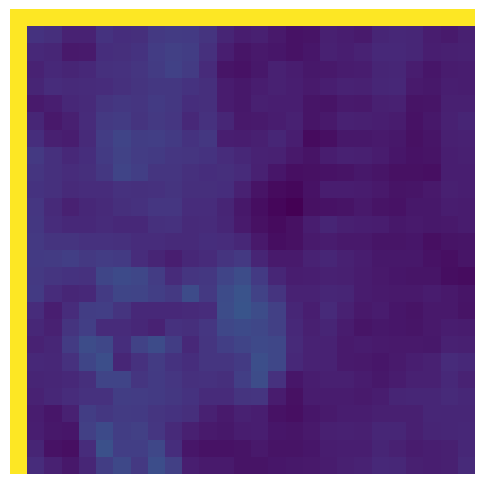

(e) NPB-REC Std.

Figure 3: Reconstructions results. Rows 1 and 3: Examples of comparing the ground truth (GT) fully sampled image to the reconstructed images obtained by the three models (1-3), NPB-REC, baseline, E2E-VarNet trained with Dropout, and the NPB-REC std. map at accelerations R=4𝑅4R=4, R=8𝑅8R=8, respectively. Rows 2 and 4: The corresponding annotated ROIS of Nonspecific white matter lesions.

5.2 Uncertainty Assessment

We calculated the mean value of the std. maps, obtained by our method and the Monte Carlo Dropout method, for all images in the inference set and utilized it as an uncertainty measure. The correlation between these uncertainty measures and reconstruction error (MSE) is depicted in Fig. 4. Our NPB-REC uncertainty measure exhibits a higher correlation with the Reconstruction error compared to Dropout (Pearson correlation coefficient of r=0.93𝑟0.93r=0.93 vs. r=0.89𝑟0.89r=0.89). Further, fig. 4LABEL:sub@fig3:c demonstrates our uncertainty measures correlate better with the acceleration rates used during acquisition. These outcomes, in turn, indicate the ability of our uncertainty measure to detect unreliable reconstruction performance. It is worth mentioning that the strong linearity of the correlation exhibited was preserved even for higher acceleration rates and when we repeated the same experiments on the knee test set (in all cases we obtained r>0.92𝑟0.92r>0.92).